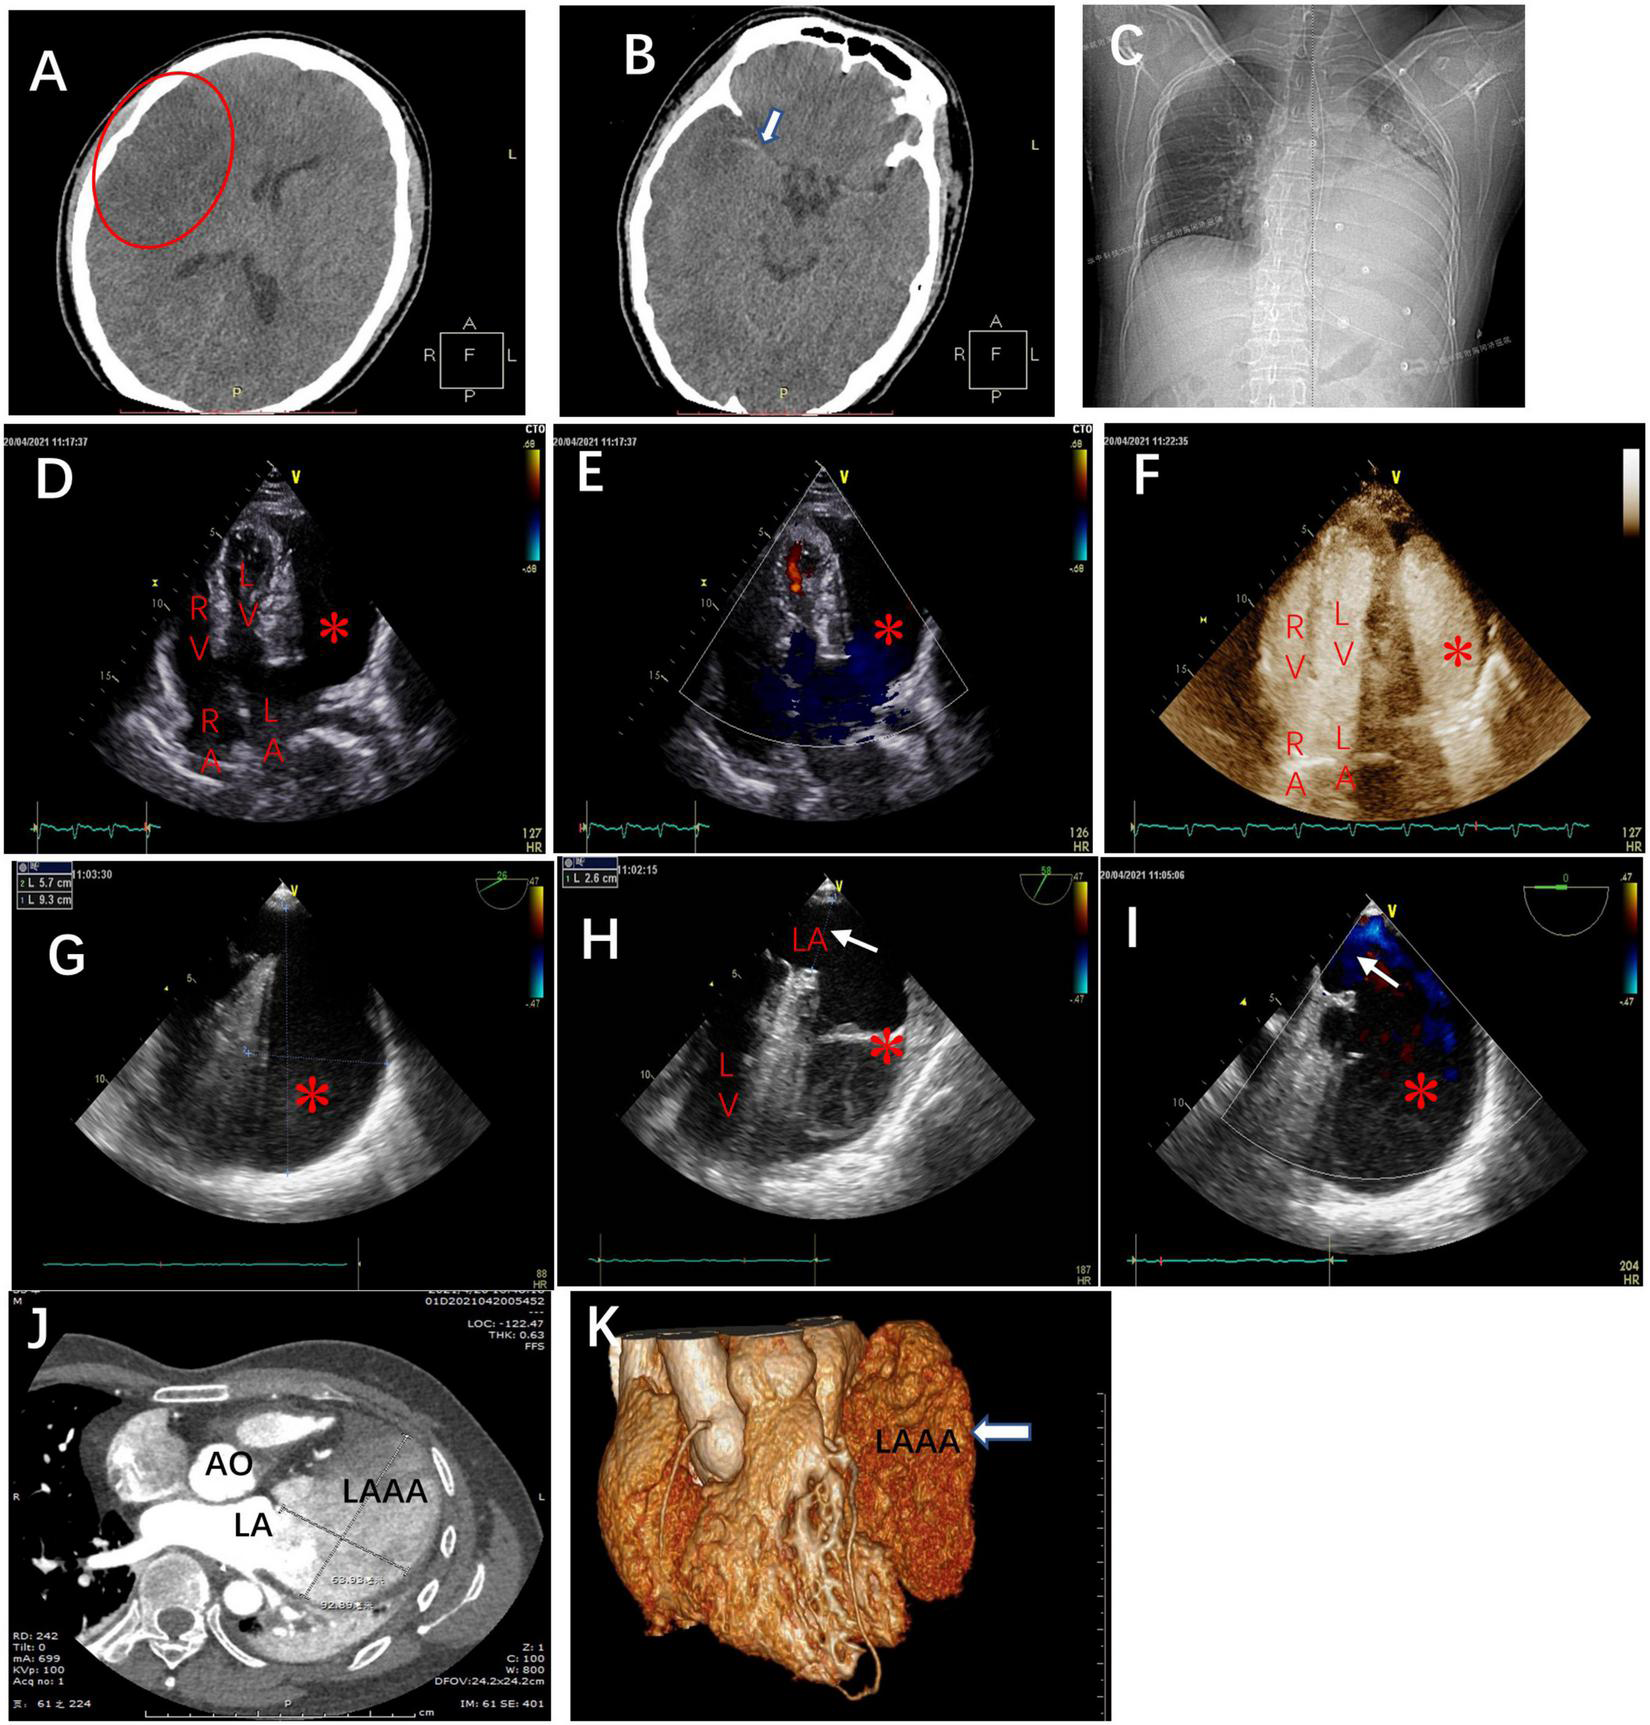

FIGURE 2

The brain computed tomography scans at admission revealed (A) massive cerebral infarction in the right-sided frontotemporal insula (red circle) and (B) the basal ganglia area with right middle cerebral artery thrombus (white arrow). (C) The chest X-ray in the cardiology department demonstrating the abnormal left heart border. Transthoracic echocardiography (TTE), apical four-chamber view (D), and the view with color doppler (E) revealing an echo-free cavity (red star) adjacent to and compressing the LV and the probable communication of the cavity with the LA; TTE with contrast showing the contrast filling in the LA and the cavity simultaneously without filling defect in the cavity (F); TEE, the mid-esophageal 2-chamber and LAA view demonstrating a giant cavity (red star) measuring 9.3 cm × 5.7 cm (G) and its connection to LA via a 2.6 cm-wide orifice (white arrow) (H) and the to-and-fro blood flows between LA and the cavity (red star) through the orifice (white arrow) (I). Axial computed tomography scan (J) and 3D reconstruction (K) demonstrate a 9.3 cm × 6.4 cm × 3.8 cm giant LAAA. AO: aorta; RA: right atrium; LA: left atrium; RV: right ventricle; LV: left ventricle.

The chest x-ray revealed a greatly enlarged left border of the heart (Figure 2C). Transthoracic echocardiography (TTE) (Vivid E9; GE Healthcare, Norway) revealed a giant echo-free cystic structure adjacent to the posterolateral wall of the left ventricle (LV) and compressed the anterolateral LV wall during the entire cardiac cycle (Figure 2D). The apical 4-chamber views with color Doppler demonstrated that this cavity was probably related to and communicated with the left atrium (LA) via a broad neck (Figure 2E). Contrast-enhanced echocardiography was performed then, which showed that the contrast agent filled the LA and the cystic structure was simultaneously with no filling defect (Figure 2F). Further transesophageal echocardiography (TEE) confirmed that the enlarged cavity measuring 9.3 cm × 5.7 cm was arising from the LA and communicating with the LA through a 2.6 cm-wide orifice, with a big chicken-wing morphology and with intense spontaneous echo contrast but no obvious thrombi (Figures 2G,H). To-and-fro blood flows through the orifice were detected by color Doppler image (Figure 2I). There were no other cardiac anomalies, and congenital LAAA was diagnosed. Computed tomography (CT) confirmed the echocardiographic findings and showed a giant LAAA measuring 9.3 cm × 6.4 cm × 3.8 cm that was compressing the LV wall (Figures 2J,K).